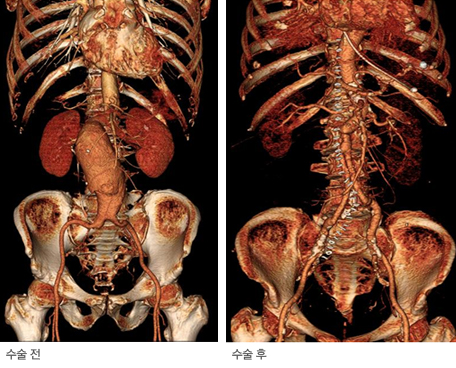

대동맥류 CT 3D 영상

복부대동맥류 수술 전후 CT 3D 영상